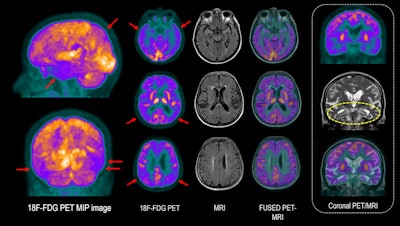

75-year-old woman with anosmia, bradykinesia, mild resting tremor in the right arm, and cognitive impairment. Patient is currently on levodopa treatment, with improvement of motor symptoms. Brain F-18 FDG PET scan shows decreased metabolism in the temporal and parietal lobes (red arrows), with left predominance. To a lesser extent, a slight decrease in cortical metabolism is observed in the frontal regions. MRI shows mesial temporal lobe atrophy with slight decrease in bilateral hippocampal volume (MTA 2) (yellow circle), with reduced metabolism evident in PET images. PET/MRI reflects cortical involvement with Alzheimer's disease-type neurodegenerative pattern.